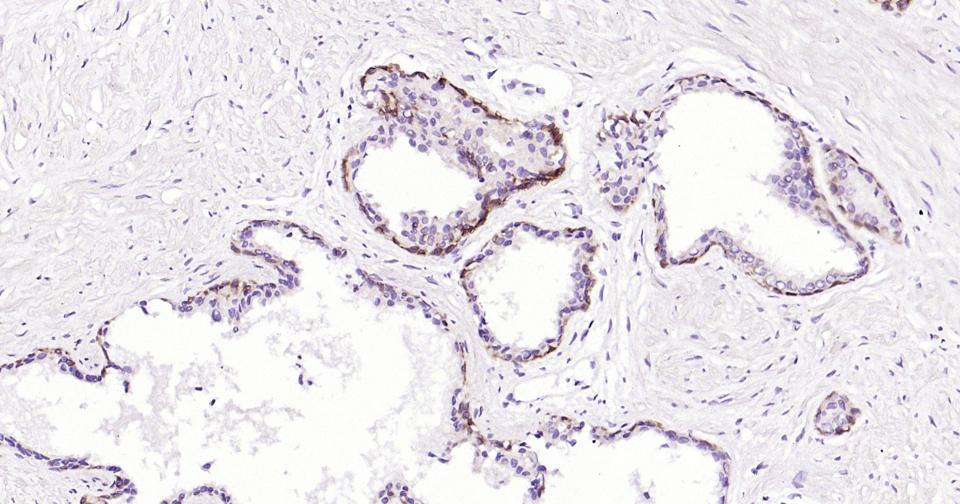

Paraformaldehyde-fixed, paraffin embedded Human Prostate; Antigen retrieval by boiling in sodium citrate buffer (pH6.0) for 15 min; Antibody incubation with Cytokeratin 5 Monoclonal Antibody, Unconjugated(bsm-34181M) at 1:200 overnight at 4°C, followed by conjugation to the SP Kit (Mouse, sp-0024) and DAB (C-0010) staining.